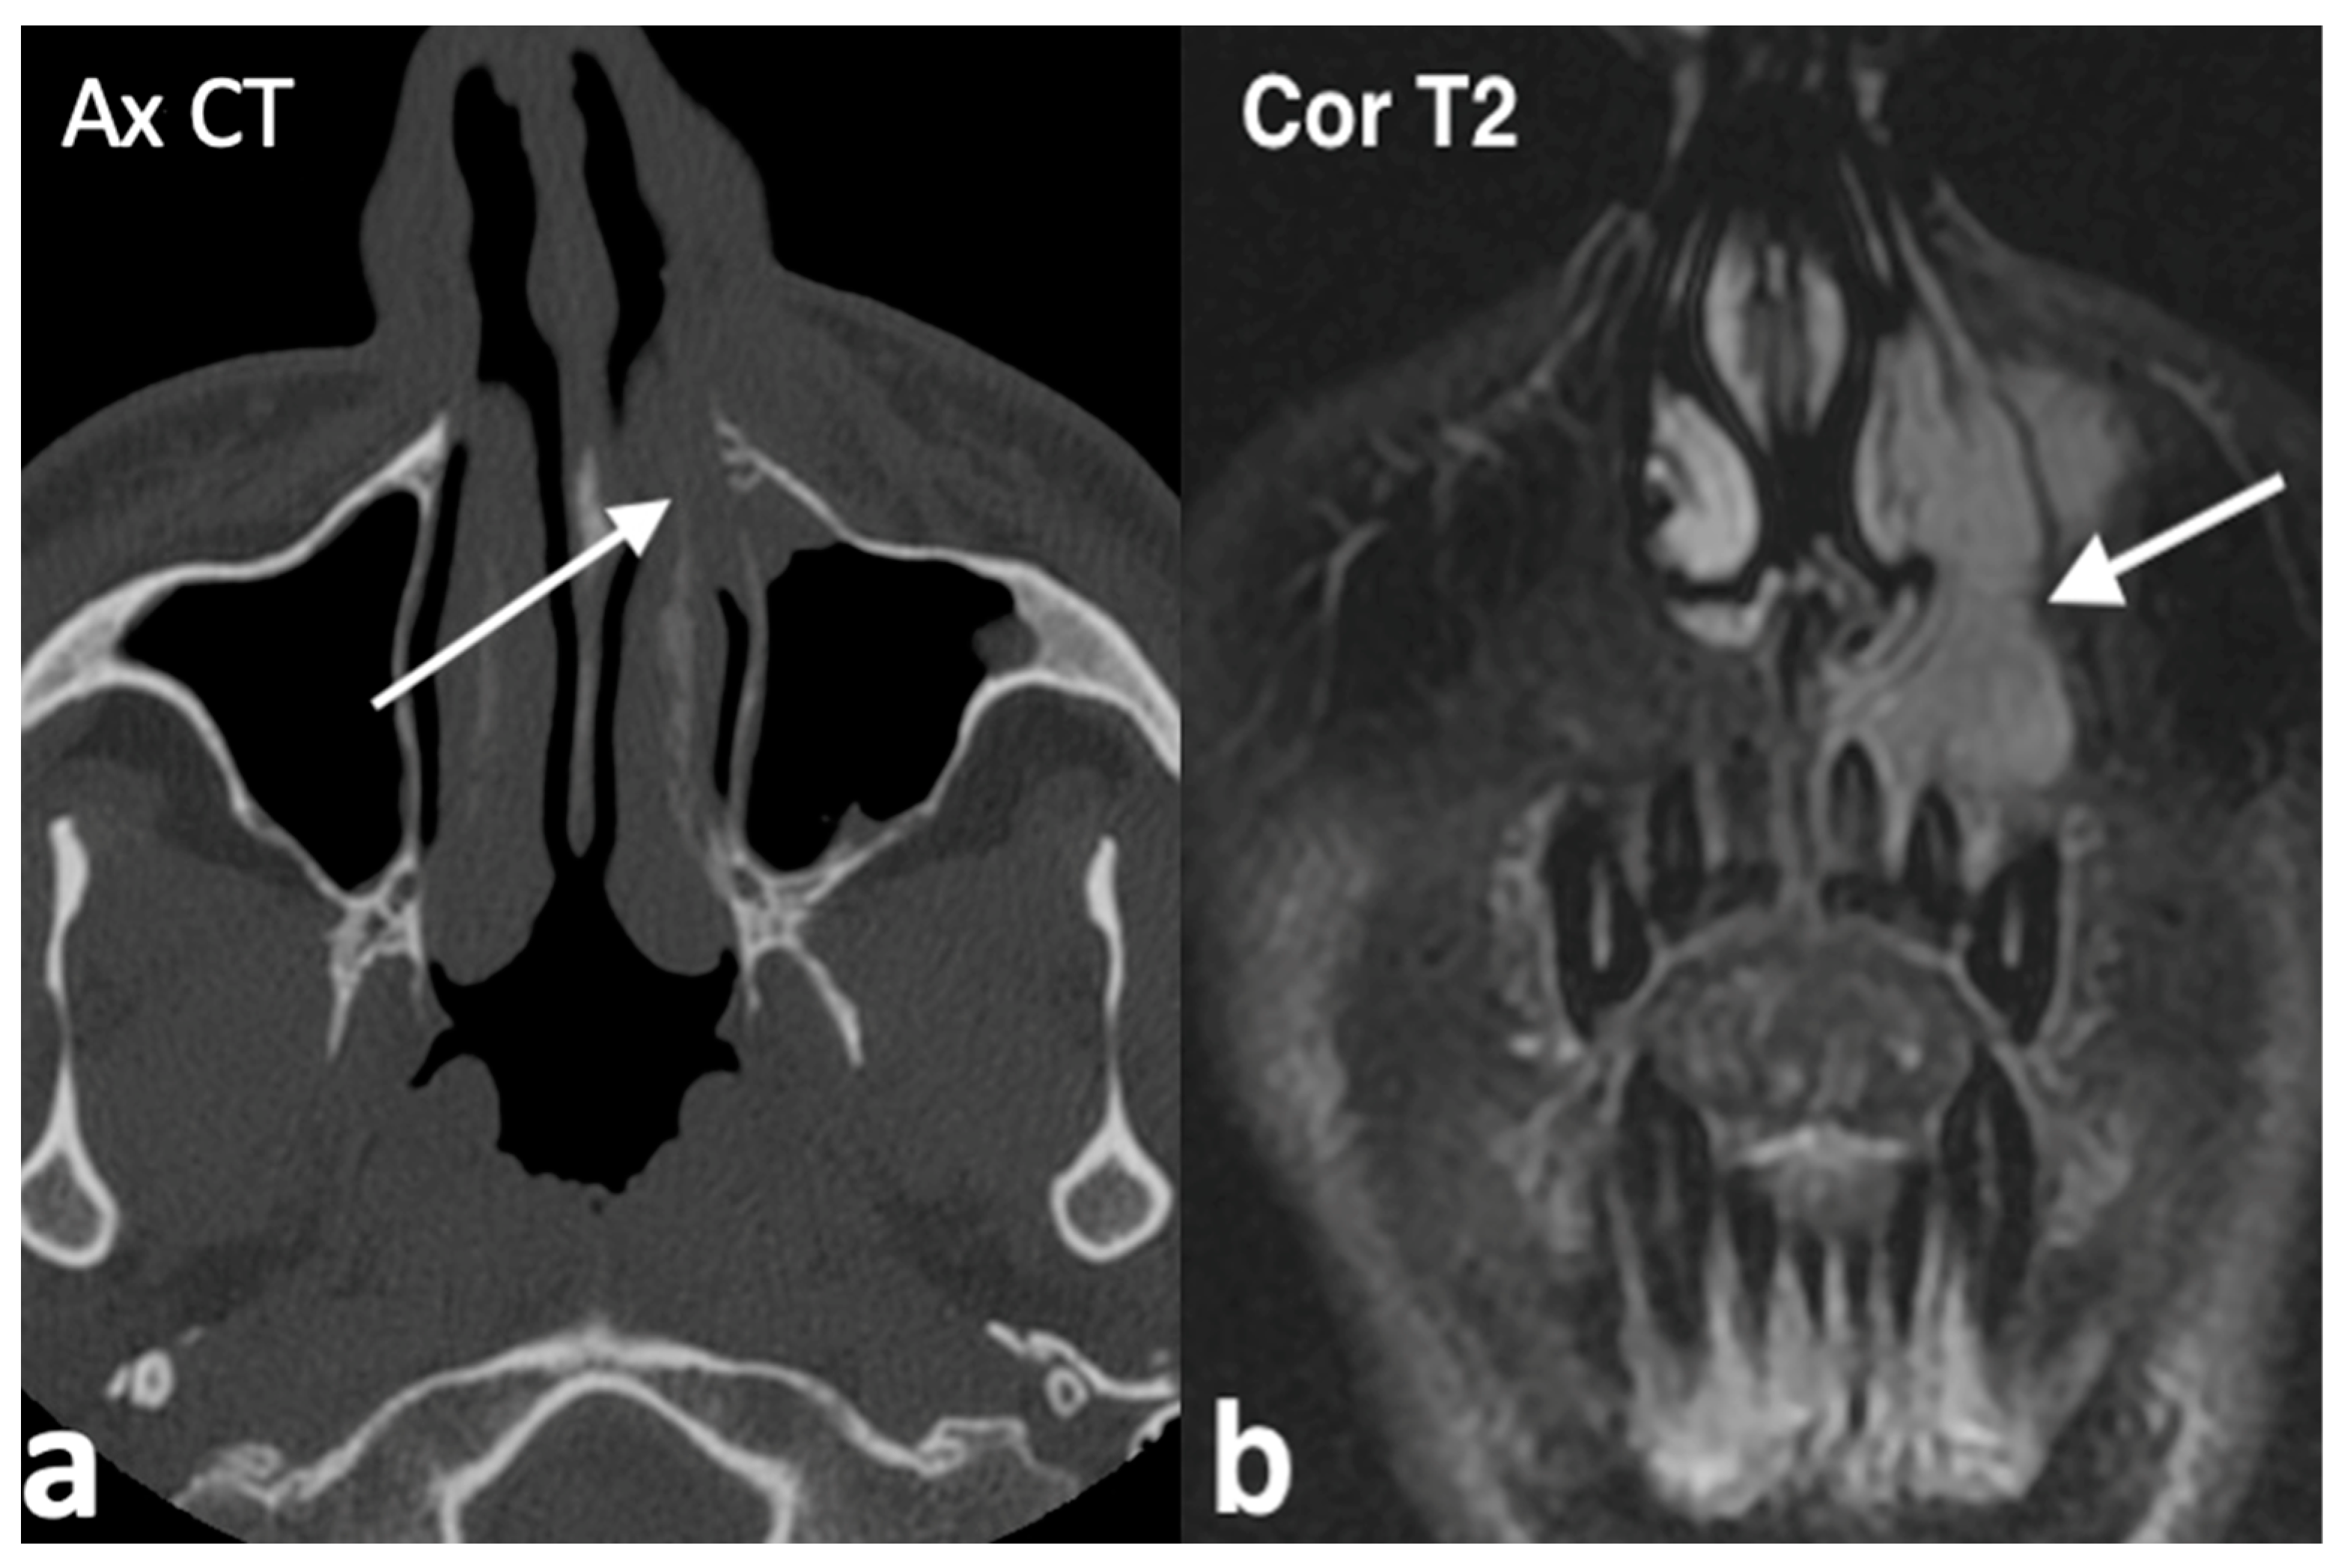

3.1.2. Rinolith

3.1.3. Inverted Mesiodens